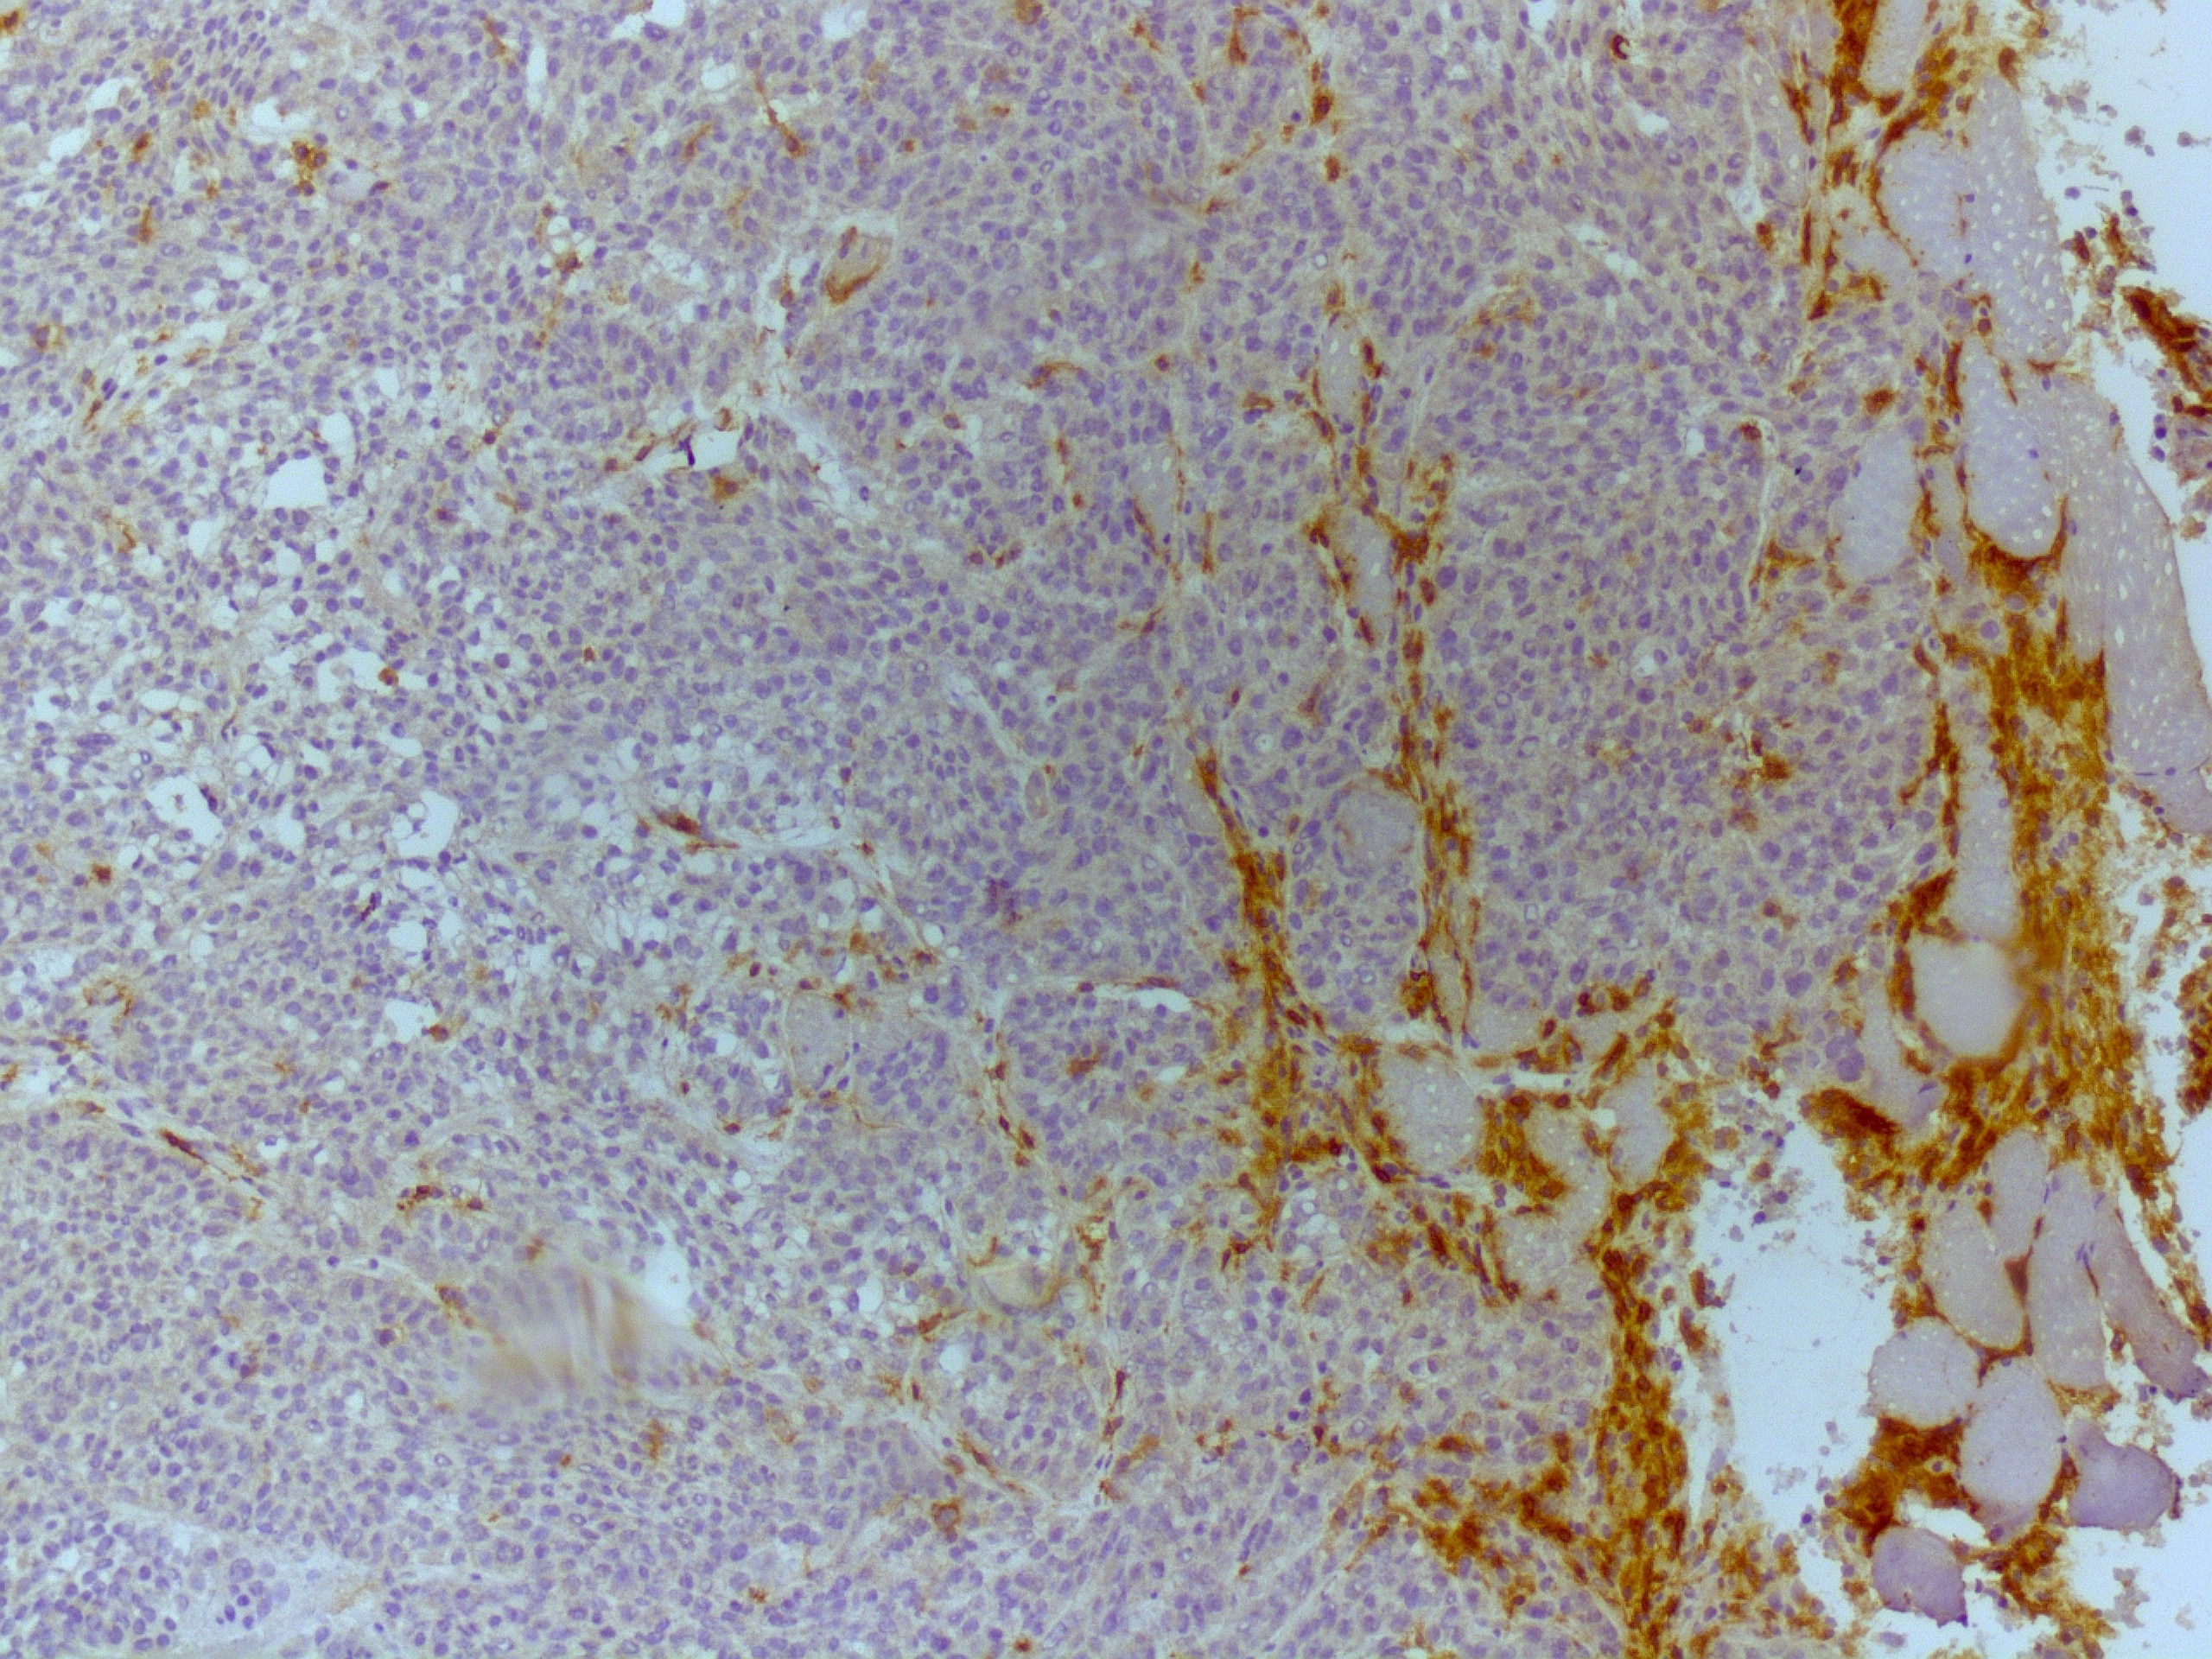

CXCL5/ENA‑78 in Human Colon Cancer Tissue. CXCL5/ENA‑78 was detected in immersion fixed paraffin-embedded sections of human colon cancer tissue using Mouse Anti-Human CXCL5/ENA‑78 Monoclonal Antibody (Catalog # MAB254) at 5 µg/mL for 1 hour at room temperature followed by incubation with the Anti-Mouse IgG VisUCyte™ HRP Polymer Antibody (VC001). Before incubation with the primary antibody, tissue was subjected to heat-induced epitope retrieval using Antigen Retrieval Reagent-Basic (CTS013). Tissue was stained using DAB (brown) and counterstained with hematoxylin (blue). Specific staining was localized to cytoplasm in epithelial cells and secreted protein. Staining was performed using our protocol for IHC Staining with VisUCyte HRP Polymer Detection Reagents.